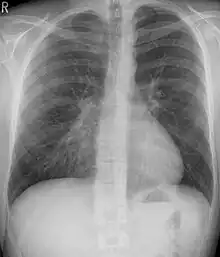

Chest x-rays are also useful in the diagnosis. The chest x-ray in pectus excavatum can show an opacity in the right lung area that can be mistaken for an infiltrate (such as that seen with pneumonia).[20] Some studies also suggest that the Haller index can be calculated based on chest x-ray as opposed to CT scanning in individuals who have no limitation in their function.[21]

Pectus excavatum is initially suspected from visual examination of the anterior chest. Auscultation of the chest can reveal displaced heart beat and valve prolapse. There can be a heart murmur occurring during systole caused by proximity between the sternum and the pulmonary artery.[15] Lung sounds are usually clear yet diminished due to decreased base lung capacity.[16]